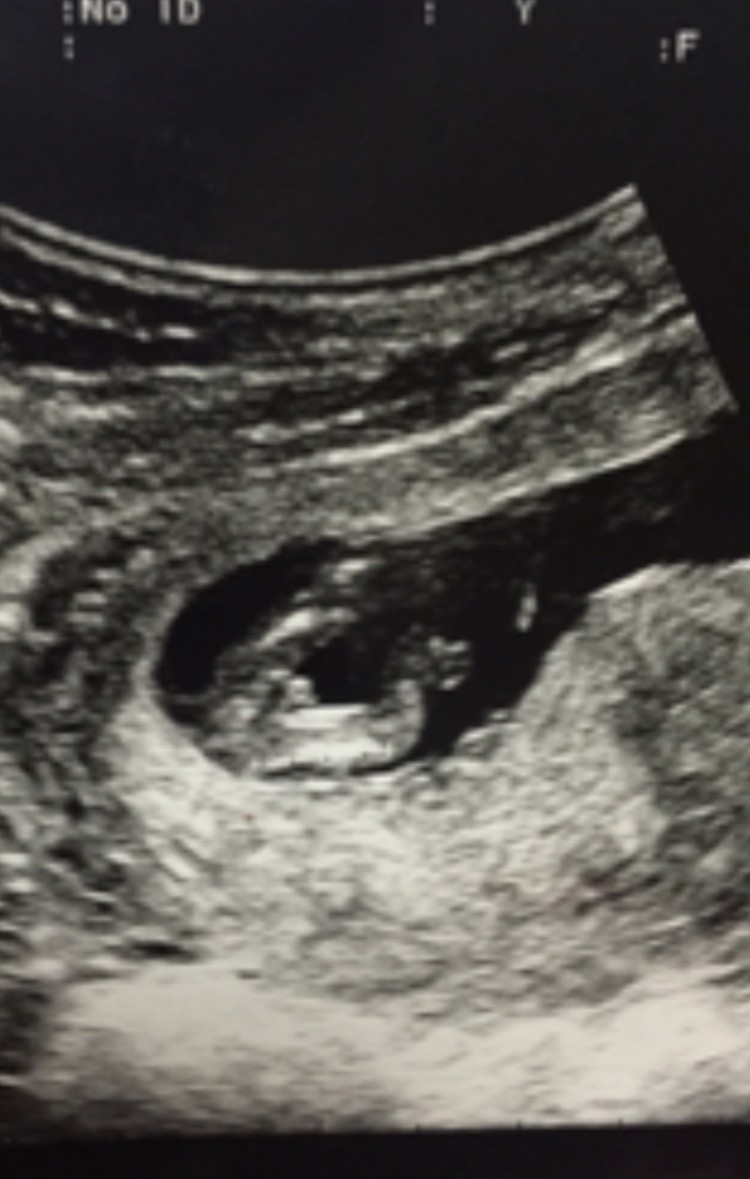

Witam w 19 tygodniu ciąży dowiedziałam się ze będę miała dziewczynkę w 20 tyg okazało się jednak , że to chłopak. Sama już nie wiem bo na jednym usg widać na pewno dziewuche a na drugim chłopca. Może to pempowina ?? Może ktoś mi pomoże rozwiązać ta zagadkę

• 4A8F5FF1-76CA-4DE0-AC12-5EDF08E820F2.jpg

4A8F5FF1-76CA-4DE0-AC12-5EDF08E820F2.jpg

596,4 KB · Wyświetleń: 23 662